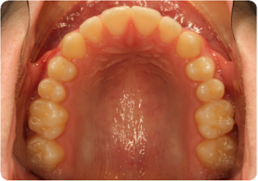

Each case shows the front view and an arch or side view, before and after BioLign Method-guided treatment.

All cases treated within 6–12 months.

Overlapping teeth resolved through arch form restoration